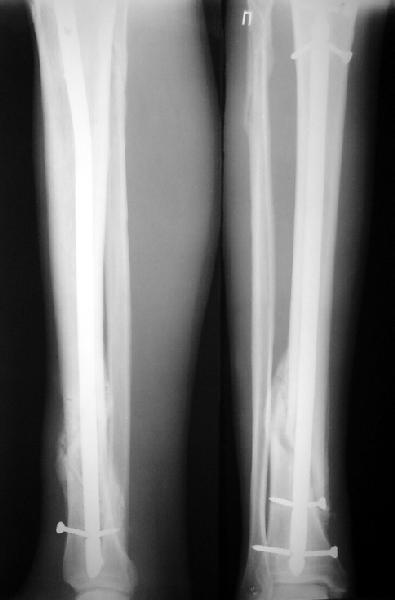

JOM> Вы не послали послеоперационный снимок, поэтому трудно судить о

JOM> состоянии редукции после операции.

А зачем о ней судить - речь ведь не об этом. Мы, помнится, обсуждали возможность ранней нагрузки после остеосинтеза.

JOM> Установка с медиальной стороны гвоздя в области дистального фрагмента

JOM> дополнительного шурупа помогло бы Вам репонировать и удержать перелом

Да, конечно. Но сочли, что и достигнутое положение приемлемо. Тем более, для non-compliant и low demanding пациента.

А если вспомнить лечение аналогичных повреждений функциональными брэйсами (Sarmiento), там рентгенограммы могут быть еще менее привлекательными, однако результаты вполне приемлемы.